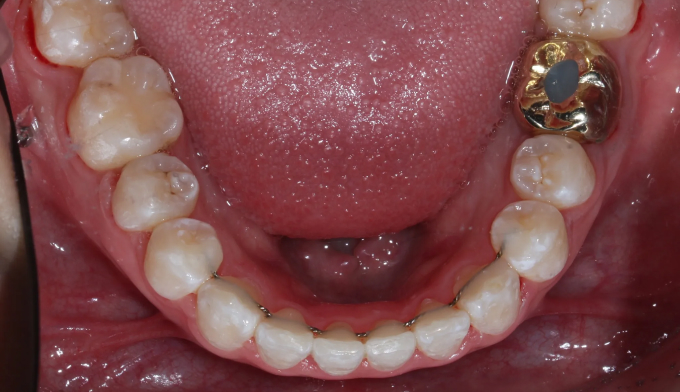

개방교합은 양쪽 어금니가 잘 맞닿아 있는데도 앞니가 위아래로 떠서 맞물리지 않는 경우를 말합니다.

이 케이스는 앞니의 치열도 불규칙합니다.

미니스크류를 이용하여 어금니 교합을 변화시켜 개방교합을 해소하였습니다. 이와 동시에 어금니의 후상방 이동으로 앞니 배열공간을 만들었고 앞니를 가지런하게 배열시킬 수 있었습니다.

치아교정이 진행되면서 구강위생관리가 좋지않아 잇몸 염증과 초기 충치가 다수 관찰되었습니다.